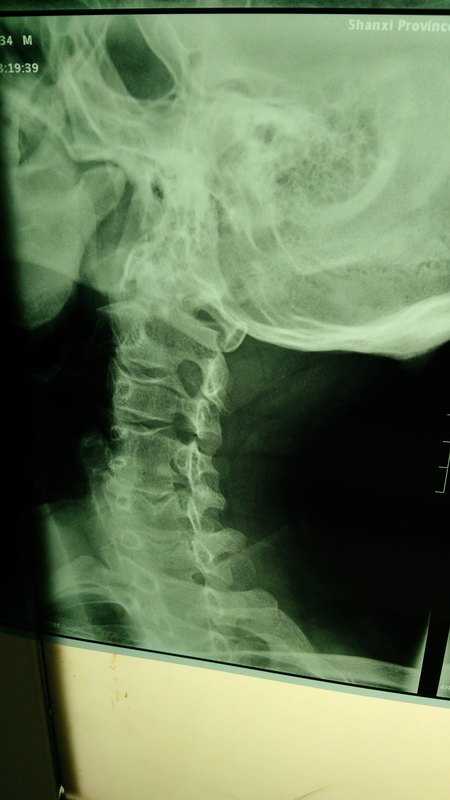

頸椎病引起的頭暈,是頸椎病所有病癥里面最常見的。不過,頭暈不一定是因為患有頸椎病!高血壓亦能引起頭暈!今天,我們就一起分析一下頸椎病和高血壓引起頭暈的區(qū)別 一、高血壓頭暈: 高血壓早期多無癥狀,偶爾體檢時,發(fā)現(xiàn)血壓增高,或者在精神緊張、情緒激動或勞累后感覺頭暈、頭痛、眼花、失眠、乏力、注意力不集中等癥狀。其中頭暈為高血壓最為常見的癥狀,多為持續(xù)性,但非陣發(fā)性,一般不伴視物模糊、耳鳴、聽力下降、頭部持續(xù)性沉悶不適,嚴(yán)重時會影響生活質(zhì)量。 二、頸椎病頭暈: 頸椎病(椎動脈型)病人常見的表現(xiàn)。病人因頸部的活動和體位改變?nèi)缟煺埂⑶扒?、旋轉(zhuǎn)等而誘發(fā)和加重眩暈、惡心、頭痛等。這類病人頸部都有酸麻、脹痛、僵硬等癥狀,少數(shù)病人伴有復(fù)視、眼顫、耳鳴及耳聾。這就是頸椎病和高血壓引起頭暈的區(qū)別。 了解了頸椎病和高血壓引起頭暈的區(qū)別以后,一起來了解一下治療頸椎病頭暈的方法: 1、 物理治療: 如頸椎牽引、頸椎手法按摩、電針及穴位貼、熱療等物理治療。 2、 靜脈輸液治療: 如脫水、擴(kuò)張血管、補鈣、營養(yǎng)神經(jīng)等藥物,能快速而有效的緩解頭暈癥狀。 3、 加強(qiáng)頸椎操鍛煉: 金龜縮頭或頸肩部對抗(頭極度后仰、肩盡力上聳,直到頸部酸脹、微痛為宜,以此反復(fù)連續(xù)10~15分鐘/次,每日3次)對于“頸椎病”所引起的高血壓,臨床上俗稱為假性高血壓,查一個“頸椎病MRI”就可以明確診斷了,這兩種病都有頭暈癥狀,但治療方法卻天差地別。 百年神貼根據(jù)患者的具體患病原因、患者年齡、病情發(fā)展程度等要素一對一為患者量配藥,更是將治療的效果發(fā)揮到極致,從而達(dá)到徹底治療頸椎病的目的,為頸椎病患者解決了最大的難題。